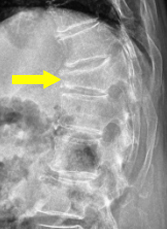

骨粗鬆症性椎体骨折のX線。矢印の部位の椎体がつぶれています。